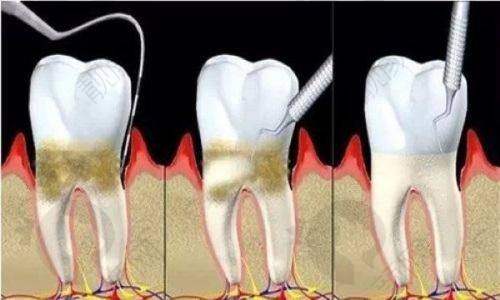

医院还引进了大量海内外精良的口腔诊疗设备。3D影像口腔CBCT系统能360度扫描口腔结构,精密定位牙槽骨、神经管等关键部位,为种植牙、正畸等手术提供精细数据支持。数字化种植导航系统通过计算机模拟种植路径,医生可以像“开导航”一样精细操作,减少手术创伤和误差。根管显微镜、超声骨刀让牙髓治疗、拔牙等操作更精细,患者体验更舒适。医用包装封口机、数字化高压灭菌器严格遵循消毒流程,避免交叉感染。